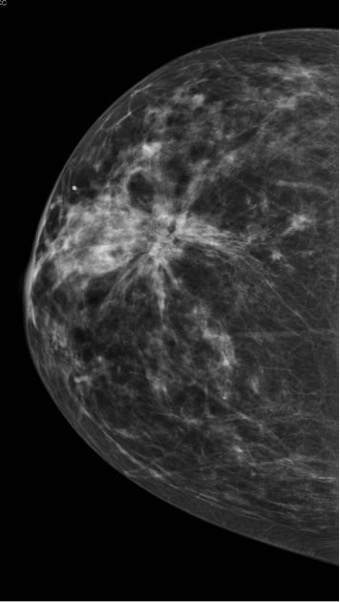

- Found on routine mammography

- Architectural distortion with irregular borders and microcalcifications

- No interventions needed outside of routine imaging

- Mammography often shows low-intensity, spiculated masses that are indistinguishable from spiculated carcinomas

- Management

- Biopsy reveals fibroelastic cores with radiating ducts and lobules

- Excision is recommended (though controversial) and is often definitive

- Mammogram shows dense pattern